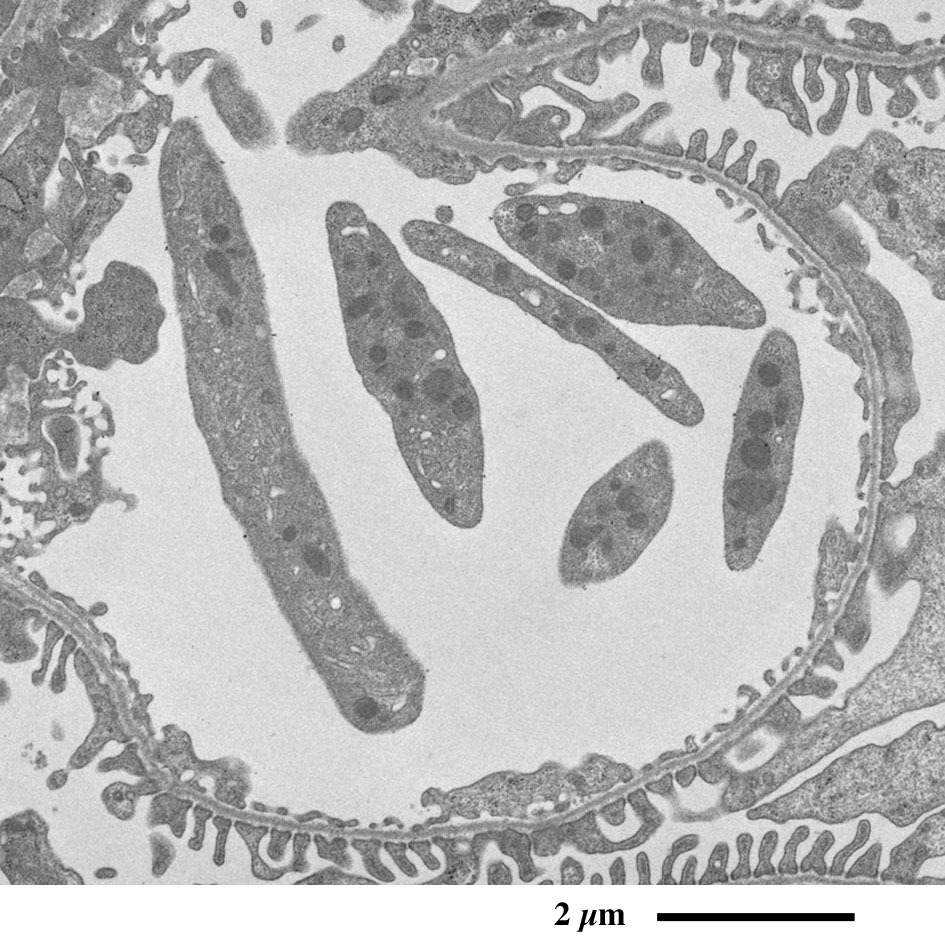

【 超薄切片の透過型電子顕微鏡画像 】

Transmission electron microscopic image of ultrathin section

近位尿細管

原尿に含まれるグルコースや電解質、水など身体に必要な物質を再吸収するため、

上皮細胞の頂上部に微絨毛が並んで表面積を増大しています。